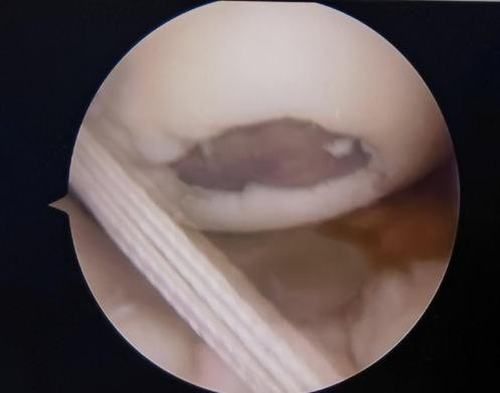

關(guān)節(jié)鏡下軟骨損傷

經(jīng)患者同意后,李鵬主任手術(shù)團隊制定詳細手術(shù)方案。手術(shù)如期進行,經(jīng)團隊密切配合,對幾位患者分別順利完成關(guān)節(jié)鏡下膝關(guān)節(jié)鏡鏡檢、關(guān)節(jié)清理、股薄肌半腱肌取腱移植術(shù)、前交叉韌帶重建術(shù)、軟骨損傷微骨折術(shù)、半月板縫合修整術(shù)等。

鏡下重建前交叉韌帶走形、張力良好